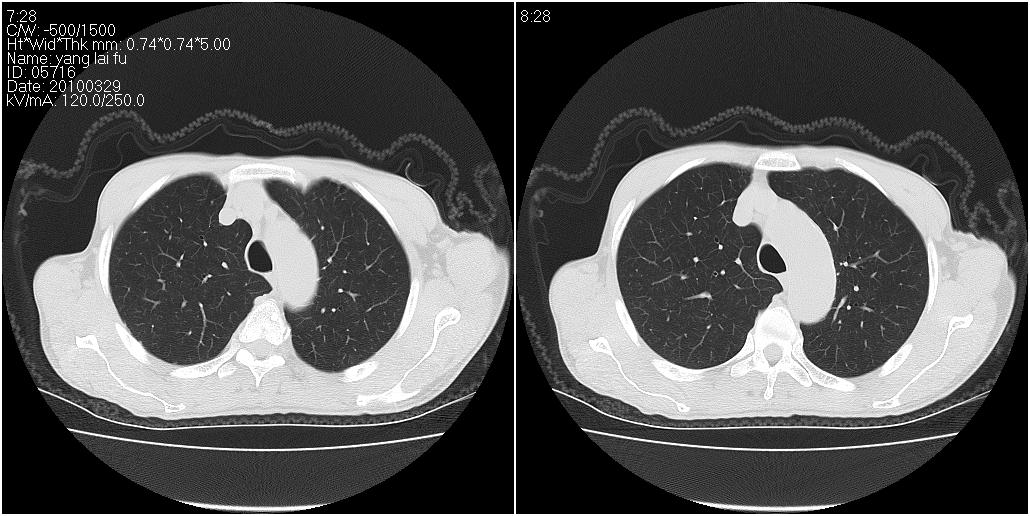

标题: CT25416:男性,70岁。胸片发现右下肺斑片状阴影 [打印本页]

标题: CT25416:男性,70岁。胸片发现右下肺斑片状阴影

1)右肺中叶慢性炎症并支气管扩张,节段性肺不张。2)两肺下叶支气管扩张。

1)右肺中叶慢性炎症并支气管扩张,节段性肺不张。2)左肺下叶支气管扩张